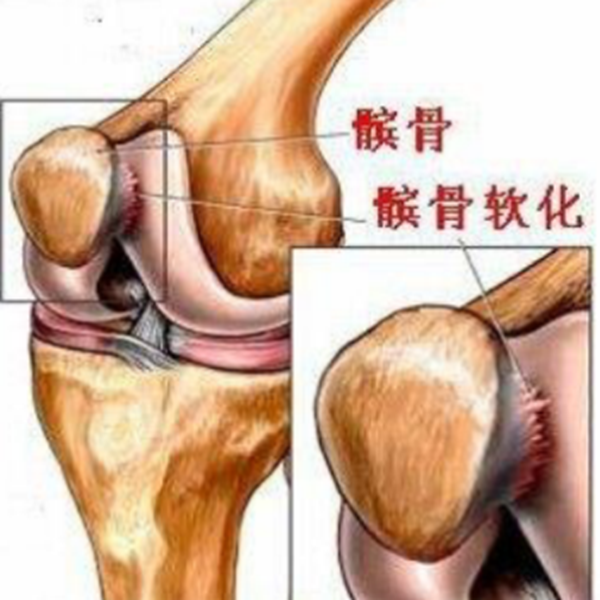

髌骨软化症(chondromalacia Patellae,CMP)又称髌骨软骨炎、髌骨软骨软化症,是一种以膝关节疼痛为主要临床症状的多病因造成的疾病。Budiger 于 1906 年描述了外伤引起关节软骨软化和纤维化;1917年Aleman提出“髌骨软骨软化”病名后一直沿用至今。其主要病理变化是软骨的退行性改变,包括软骨肿胀、碎裂、脱落,最后股骨髁的对应部位也发生同样病变,发展为髌骨关节骨性关节炎。

关节镜下可将髌骨软化分为5级

0级:正常关节软骨

Ⅰ级:关节软骨失去珍珠样外观而变得较暗淡,局部软化,肿胀区或纤毛化区的直径<0.5cm。

Ⅱ级:关节软骨软化区内出现毛刷状或纤毛化改变,深达1-2mm,直径≤1.3cm。

Ⅲ级:软骨的毛刷状或纤毛化改变达关节软骨厚度一半以上,直径>1.3cm,关节软骨表面类似蟹肉样改变,表面有多发软骨碎片附着其下的软骨。

Ⅳ级:关节软骨全层受侵,软骨下骨暴露,表现为进展期髌股关节炎。

Ⅰ~Ⅱ级为早期,主要保守治疗,Ⅲ~Ⅳ级为进展期,需要手术及关节镜治疗。